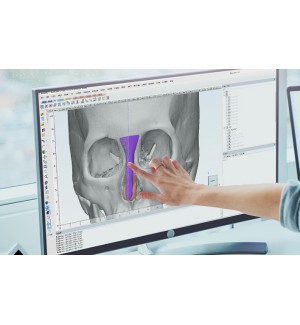

Nền tảng phần mềm hình ảnh y tế cho phẫu thuật thẩm mỹ cung cấp các giải pháp cấy ghép tùy chỉnh cá nhân hóa .

Trước khi tiến hành phẫu thuật, nhân viên y tế có thể phân tích thông tin bệnh nhân thông qua phân tích tự động AI, thiết lập kế hoạch phẫu thuật, thiết kế cấy ghép và dự đoán phẫu thuật sau phẫu thuật.

Phần mềm phân tích hình ảnh y tế tự động cho phẫu thuật thẩm mỹ:

Chương trình dành riêng cho thiết kế FITme: